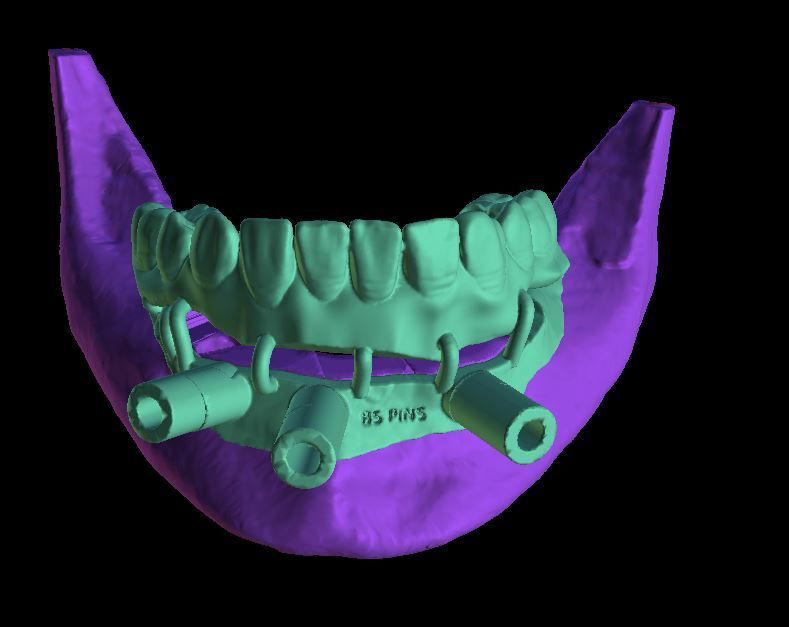

- Learn to plan implants using Blue Sky Plan

- Learn to create a surgical guide for $20 that can be printed in your office or outsourced to a commercial printer for less than $50

- Learn to use an in-office 3D printer for printing guides for as low as a few dollars each

- Gain hands on experience in planning several implant cases so that you become proficient with the software. This experience can be used in other implant planning software programs as well.

- Get very proficient with tooth supported and tissue supported surgical guides